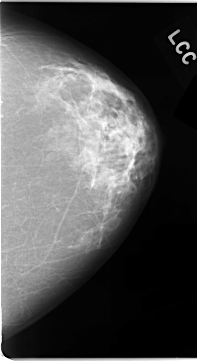

C_0034_1.LEFT_CC

LEFT_CC LINES 4688 PIXELS_PER_LINE 2552 BITS_PER_PIXEL 12 RESOLUTION 50 NON_OVERLAY